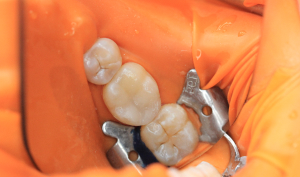

• лікування карієсу

• реставрації зубів